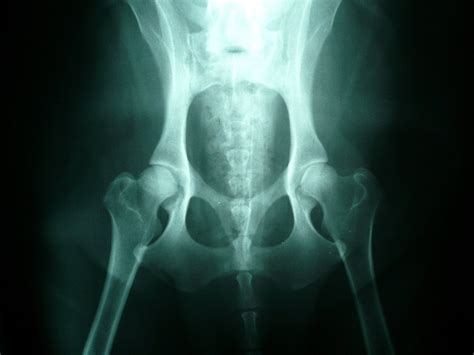

Dysplázia bedrového kĺbu sa diagnostikuje röntgenovým vyšetrením. Aby bolo možné röntgenovú snímku bedier optimálne posúdiť, musí byť táto vždy vykonaná v anestéze v štandardizovanej polohe. Narkóza psa je nevyhnutná na uvoľnenie svalov, a aby pri polohovaní na snímku nepociťoval bolesť. Ochorenie sa dá zdiagnostikovať a určiť stupeň dysplázie jedine RTG vyšetrením vykonanom v celkovej anestézii na oficiálne schválenom RTG pracovisku. Od 12 týždňov veku je možné vykonať tzv. rannú diagnostiku DBK. V prípade podozrenia na dyspláziu sa diagnostika vykonáva ihneď bez ohľadu na vek. Pre účely chovnosti je jedinec vyšetrovaný po dosiahnutí určitého veku (v závislosti od plemena od 12,18, či 24 mesiacov). Po posúdení RTG snímku na chovné účely je vyhodnotený certifikát s výsledkom, ktorý je zároveň zapísaný aj do PP. Na hodnotenie sa u nás (podobne ako vo väčšine európskych krajín) používa 5-stupňový systém, škála hodnotenia je od A - E alebo 0 až 4. Dysplázia bedrového kĺbu sa medzinárodne označuje ako HD (hip dysplasia). Vyhodnocuje sa ľavý i pravý kĺb, zápisy HD 0/0 alebo HD A/A predstavujú zdravé kĺby bez nálezu. Čím vyššie číslo (resp. písmeno), tým vyšší stupeň dysplázie.

Veterinárny lekár môže pomocou röntgenových snímkov vyhodnotiť závažnosť dysplázie bedrového kĺbu a posúdiť zmeny v bedrovom kĺbe. Zásadným hodnotiacim kritériom je „Norbergov uhol“, ktorý sa určuje dvoma líniami medzi stredmi oboch hlavíc stehennej kosti a predným okrajom kĺbovej jamky. U psa bez DBK ochorenia by mal byť uhol väčší ako 105 stupňov. Nasledujúce zmeny sú tiež znakmi dysplázie bedrového kĺbu: jamka bedrového kĺbu alebo hlavica stehennej kosti, alebo obidve sú sploštené, takže nie je zaručené optimálne zapadnutie hlavice do jamky bedrového kĺbu. Okrem toho sa dá často pozorovať vychýlenie krčka alebo hlavice stehennej kosti. Často sú už viditeľné príznaky artrózy, ako sú napríklad zmeny na prednom a zadnom okraji jamky a pri prechode z krčku stehennej kosti do hlavice.

Pri výbere chovných zvierat sú potrebné určité kritériá na vyhotovenie röntgenových snímok a ich hodnotenie. U niektorých plemien, v niektorých krajinách alebo pri odborných posudkoch, je potrebný ďalší röntgen s roztiahnutými stehnami a nadvihnutými členkami (tzv. „žabí snímok“), pretože zmeny okraja kĺbovej jamky a stehenných kostí sú tak lepšie viditeľné. Rozdelenie chovných zvierat sa uskutočňuje podľa predpisov Medzinárodnej kynologickej federácie F.C.I. Okrem röntgenových snímok sú pre ošetrenie psa rozhodujúce výsledky klinického vyšetrenia a príznaky.